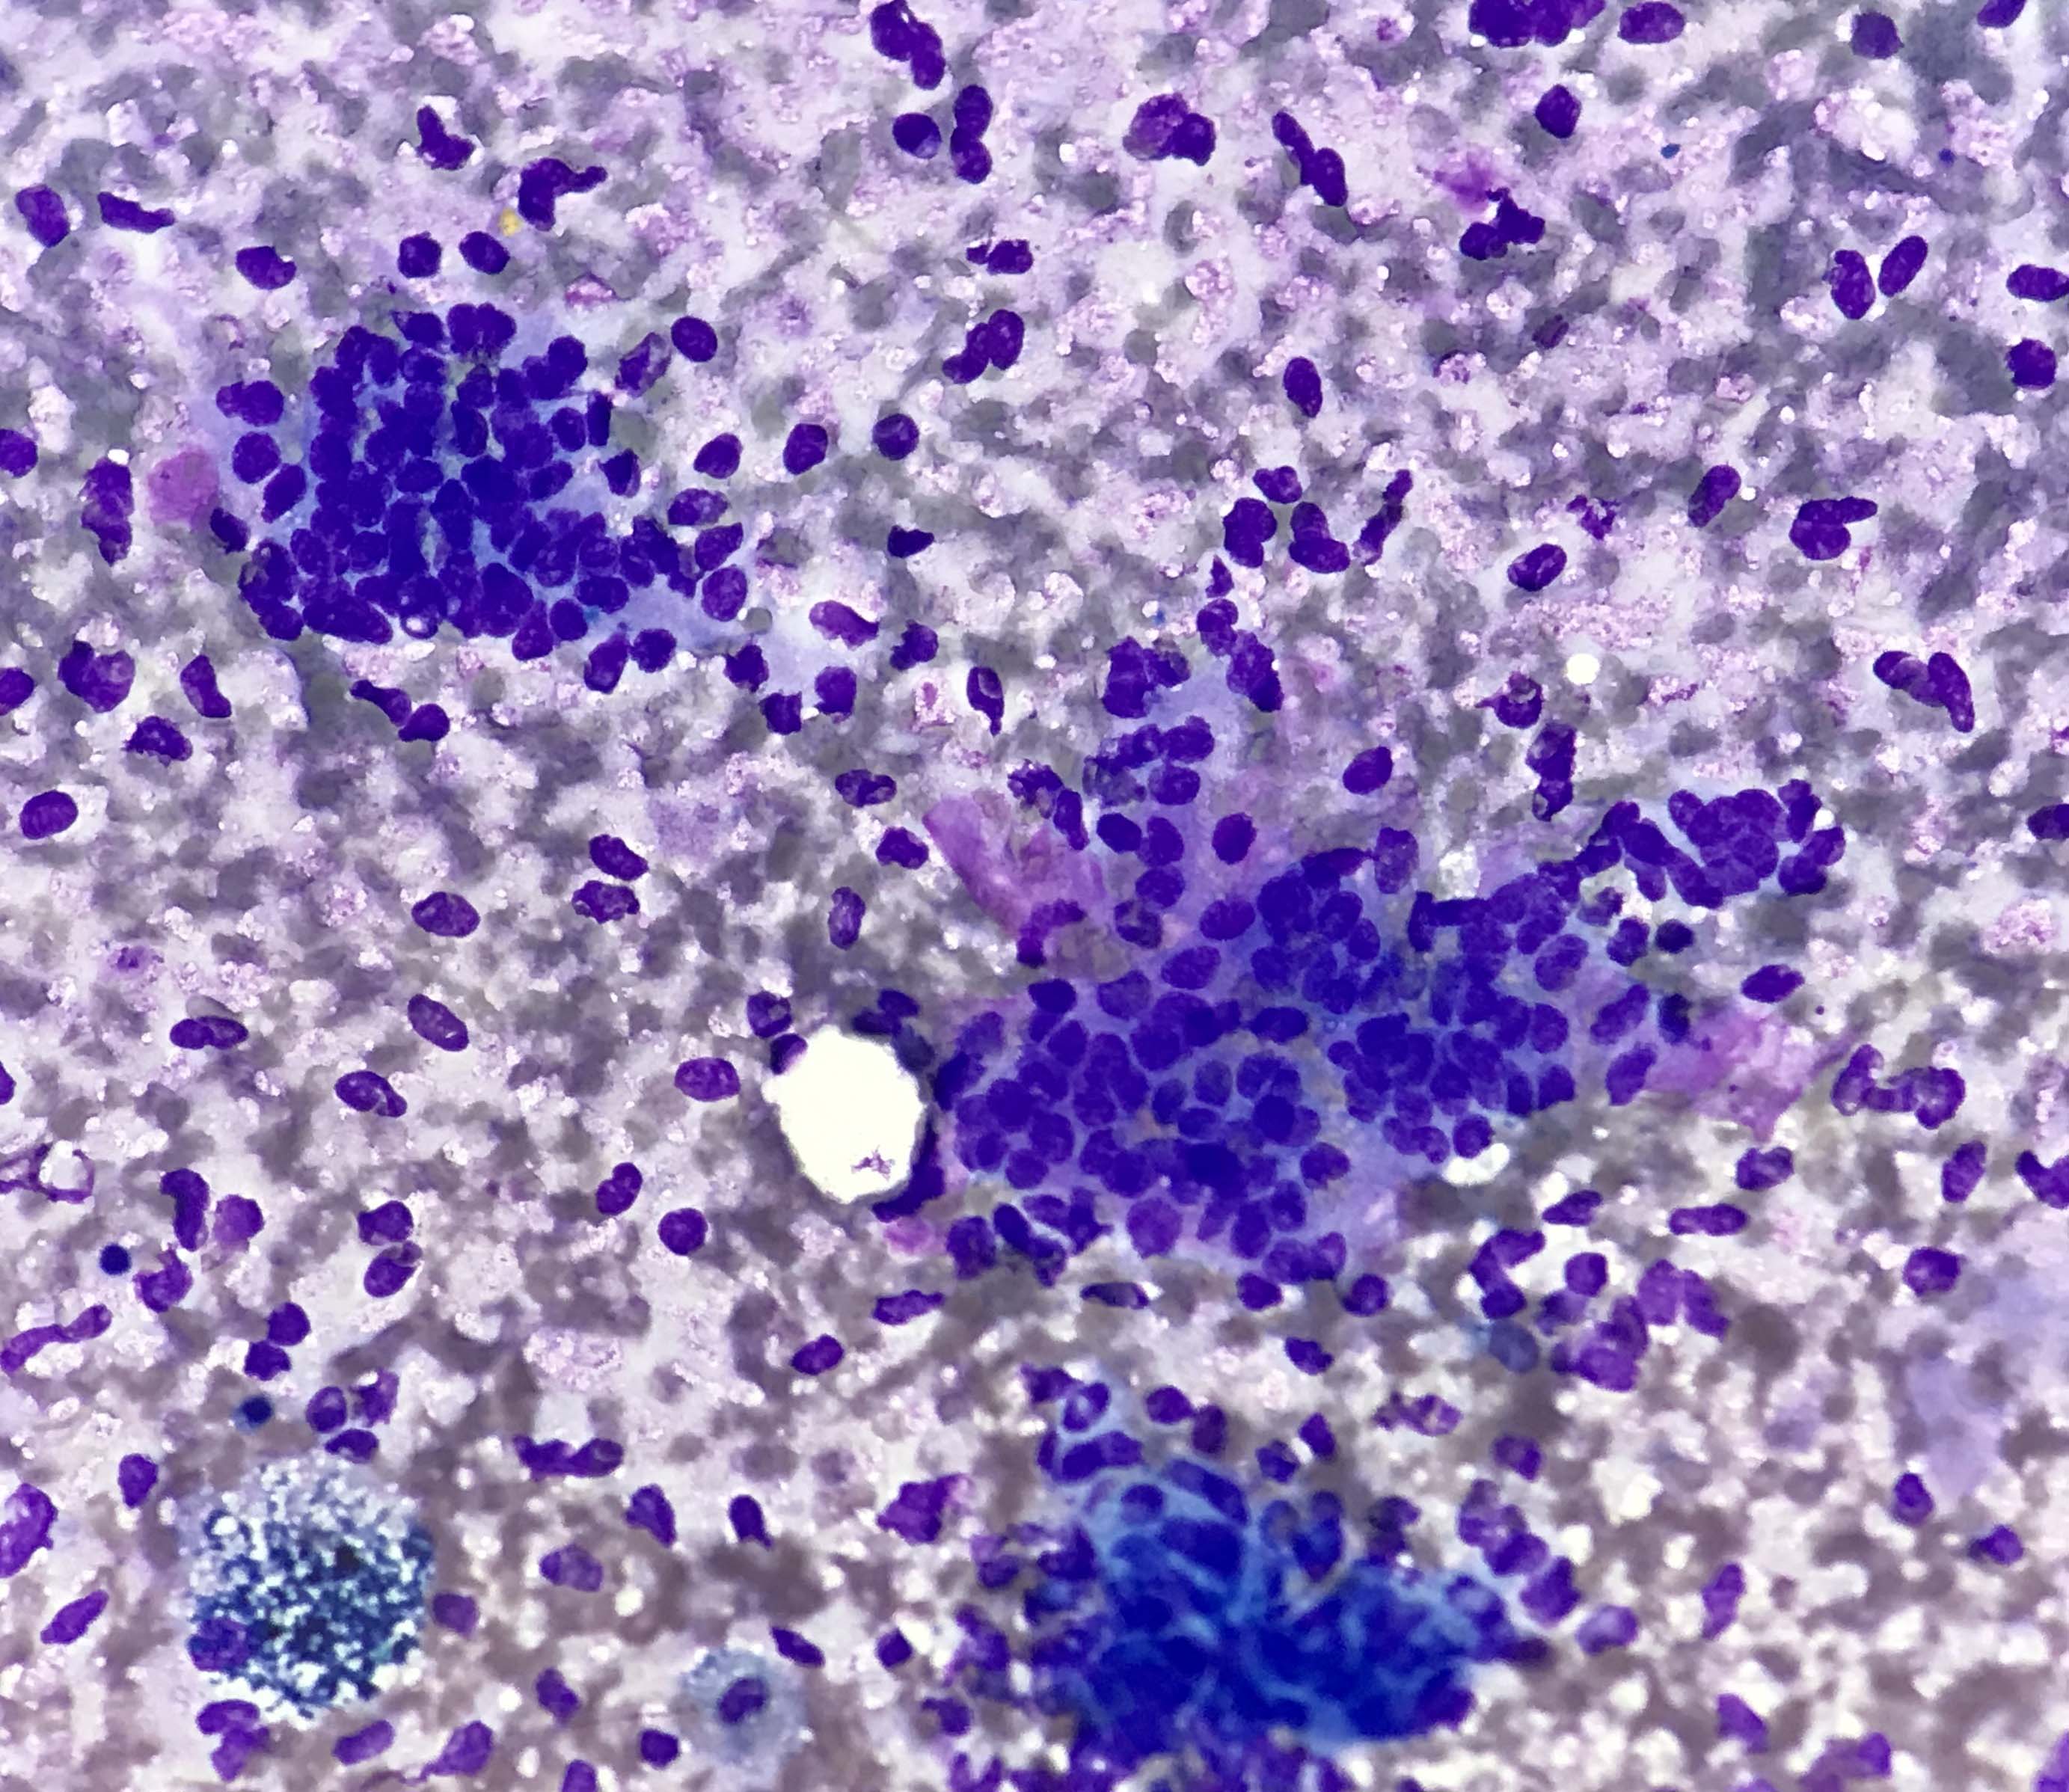

Contributed by Kelly Magliocca, D.D.S., M.P.H. and Anne C. McLean-Holden, D.M.D., M.S.

Cytology description

- Compact and cohesive cell clusters with areas of short branching of tumor cells along the periphery (Diagn Cytopathol 2013;41:206)

- Oval to round basaloid cells with high nuclear to cytoplasmic ratios, fine powdery chromatin, nucleoli with small peripheral nucleoli to inconspicuous nucleoli

- Squamous cells centrally with more abundant cytoplasm (particularly in acanthomatous variant)

- Possible limitations to FNA

- Inadequate sampling due to extensive cyst formation within the tumor

- Inability to distinguish ameloblastoma with macrocystic degeneration from ameloblastoma, unicystic type

- Inability to distinguish ameloblastoma from metastatic ameloblastoma without prior knowledge of metastatic disease

- Inability to distinguish ameloblastoma from other benign odontogenic tumors that are managed with curettage (e.g. adenomatoid odontogenic tumor, ameloblastic fibroma) (Diagn Cytopathol 2013;41:206)